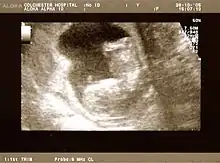

Fetus at 17 weeks

Fetus at 20 weeks

Obstetric ultrasonography is routinely used for dating the gestational age of a pregnancy from the size of the fetus, determine the number of fetuses and placentae, evaluate for an ectopic pregnancy and first trimester bleeding, the most accurate dating being in first trimester before the growth of the foetus has been significantly influenced by other factors.[24] Ultrasound is also used for detecting congenital anomalies (or other foetal anomalies) and determining the biophysical profiles (BPP), which are generally easier to detect in the second trimester when the foetal structures are larger and more developed.[25] Specialised ultrasound equipment can also evaluate the blood flow velocity in the umbilical cord, looking to detect a decrease/absence/reversal or diastolic blood flow in the umbilical artery.[26]

The safety of frequent ultrasound scanning has not been confirmed. Despite this, increasing numbers of women are choosing to have additional scans for no medical purpose, such as gender scans, 3D and 4D scans.[30] A normal gestation would reveal a gestational sac, yolk sac, and fetal pole.[31]

The gestational age can be assessed by evaluating the mean gestational sac diameter (MGD) before week 6, and the crown-rump length after week 6. Multiple gestation is evaluated by the number of placentae and amniotic sacs present.[32]